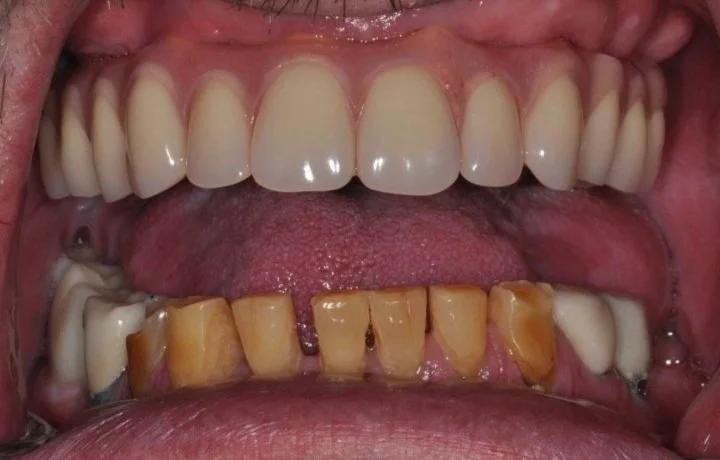

How We Restored a Front Tooth with a Dental Implant — Start to Finish

They’re what people notice first. So when a front tooth is missing or damaged — whether from trauma, decay, or failed restorations — it’s not just about replacing it. It’s about doing it perfectly in the smile.

In this case study, we’ll walk you through one of the more complicated — and rewarding — procedures we do at our practice: a front tooth dental implant. You’ll see how much thought, planning, and precision goes into restoring one small tooth… and why every step in the dental implant process matters.

Plan the End Smile result before Beginning.

We always start by planning the end result! We can do this digitally. See here for more information on our digital smile design. We also need to take a step back and understand what is important for our patient, and what risks are present in the process. Patients may need a front tooth implant for different reasons, and we want to understand those reasons and plan accordingly. We may be dealing with gum disease, bite forces, and challenging esthetics. Knowing the risks beforehand, and pre-planning the smile design digitally allows a more predictable result in the end. This is the MOST IMPORTANT STEP!

In our case study, we were managing bite forces and esthetics, which I detail in the video.

This first step also helps make sure the patient is on the same page with what to expect a final result to look like. We also go over financial details and timeline. This way the patient knows what to expect every step of the way!CBCT 3D Planning

Often using a guided technique (with a 3D printed surgical guide), we place the implant with extreme precision. It must sit in a position that supports both the future crown and the surrounding gum tissue for a natural look. The exact location is already planned prior to surgery in our CBCT software.Provisional Tooth (Temporary)

In the front of the mouth, we never leave a visible gap. A temporary tooth (provisional) is placed to shape and support the gum tissue during healing. This sculpting phase is key for a beautiful final result. I didn’t go into detail on this in our video. There are various ways to do this while the implant heals though, including a removable partial denture, an essix retainer, or immediately loading the implant with a temporary crown.Healing & Monitoring

Over the next few weeks or months, we monitor soft tissue healing. Sometimes we adjust the temporary to guide gum shaping. Patience here pays off — rushing this stage can lead to esthetic failure. One of the biggest risks in front teeth implants is gum recession!Final Crown

Once everything is stable, we place the final custom crown. Shade, translucency, shape, and surface texture are all matched to your natural teeth so the implant blends in seamlessly.